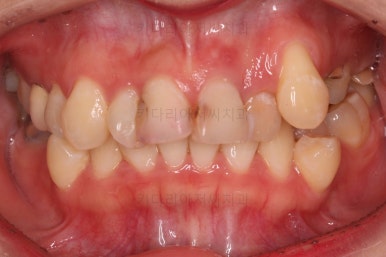

초진 시 얼굴 모습인데요.

입을 다물었을 때의 옆라인, 편안한 느낌 등 입매에 대한 부분은 양호했고요.

다만, 삐뚤고 썩은 앞니 때문에 웃는 모습이 부자연스러우셨고요.

드러나는 치아/치열의 모습이 심미적이지 못하죠.